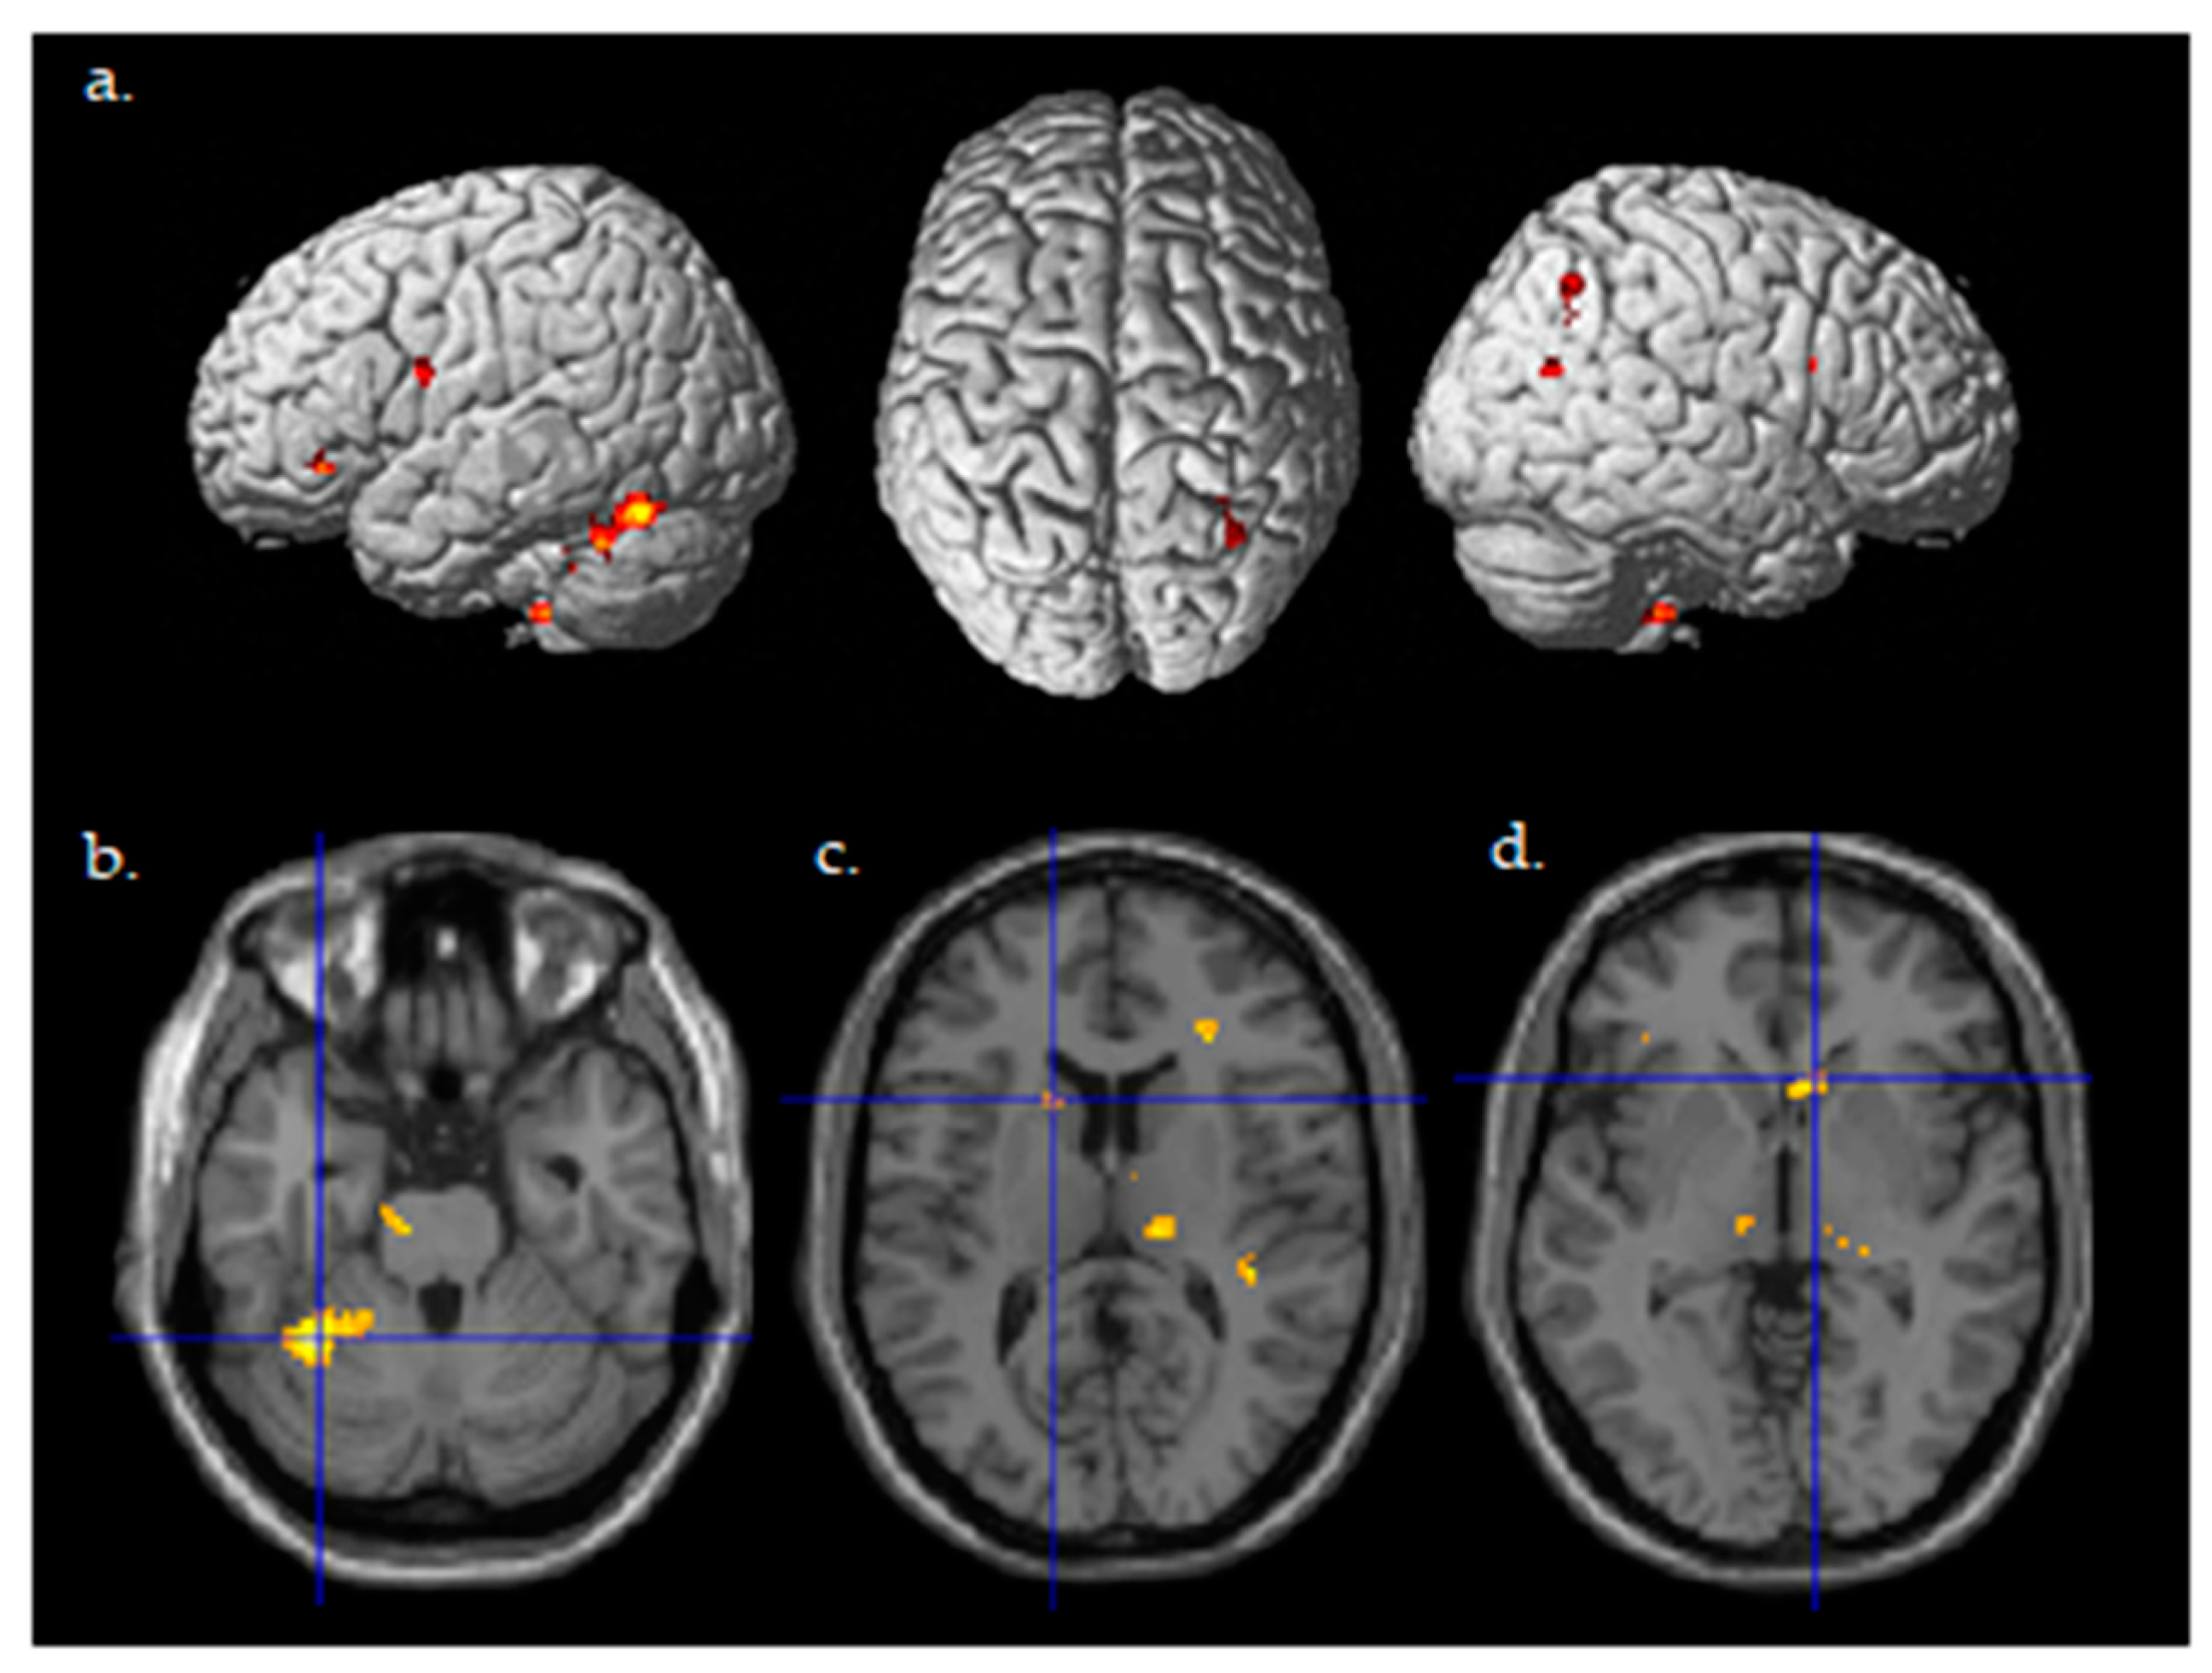

| Brain Region | Cluster Size | MNI Coordinate x, y, z | T | p |

|---|---|---|---|---|

| Cerebellum | 447 | −32, −50, −26 | 5.32 | 0.0000028 |

| Cerebellum | 77 | 8, −52, −52 | 4.52 | 0.000085 |

| Midbrain/Brain Stem | 69 | −8, −18, −20 | 4.42 | 0.00011 |

| Midbrain/Brain Stem 1 Hippocampus Thalamus | 272 | 12, −24, −10 24, −28, −10 16, −22, 8 | 5.94 4.48 4.39 | 0.0000027 0.000093 0.00012 |

| Hippocampus | 79 | −36, −18, −12 | 5.05 | 0.000024 |

| Thalamus | 24 | −8, −16, 0 | 4.27 | 0.00036 |

| Thalamus | 34 | 8, −6, 16 | 4.15 | 0.00021 |

| Caudate | 27 | −14, 14, 12 | 4.21 | 0.00018 |

| Caudate | 27 | 6, 20, −2 | 4.08 | 0.00025 |

| Frontal Operculum | 20 | 28, 32, 12 | 4.05 | 0.00046 |

| Orbital IFG | 29 | −42, 32, −8 | 4.46 | 0.000098 |

| Opercular IFG | 24 | 40, 8, 24 | 3.92 | 0.00092 |

| Medial Orbital Gyrus | 50 | 14, 6, −20 | 5.36 | 0.000011 |

| Premotor Cortex/Precentral Gyrus | 21 | −44, 2, 22 | 4.47 | 0.000095 |

| Postcentral Gyrus | 21 | 42, −10, 24 | 3.94 | 0.00035 |

| Parietal Operculum | 69 | 36, −32, 26 | 4.99 | 0.000027 |

| Precuneus/Posterior Cingulate Gyrus | 36 | 18, −40, 42 | 4.54 | 0.00008 |

| Posterior Cingulate Gyrus | 20 | −12, −40, 20 | 4.54 | 0.00008 |

| Superior Parietal Lobule Angular Gyrus | 145 | 32, −54, 44 38, −5, 34 | 4.5 3.98 | 0.00009 0.00031 |

| Middle Occipital Gyrus | 20 | 42, −66, 20 | 4.23 | 0.00017 |

| Lingual Gyrus | 21 | 6, −74, −8 | 4.12 | 0.00022 |

| Primary Auditory/Planum Temporal | 55 | 36, −28, 6 | 4.34 | 0.00013 |

| Planum Temporal | 85 | −42, −34, 4 | 5.21 | 0.000016 |

| Brain Region | Cluster Size | MNI Coordinate x, y, z | T | p | pFWE_corr |

|---|---|---|---|---|---|

| Cerebellum | 265 | −32, −50, −26 | 5.32 | 0.0000028 | 0.026 * |

| Cerebellum | 77 | 8, −52, −52 | 4.52 | 0.000085 | 0.110 |

| Caudate | 27 | −14, 14, 12 | 4.21 | 0.00018 | 0.025 * |

| Caudate | 23 | 6, 20, −2 | 4.08 | 0.00025 | 0.032 * |

| PMv | 2 | −44, 4, 20 | 3.75 | 0.00056 | 0.063 |